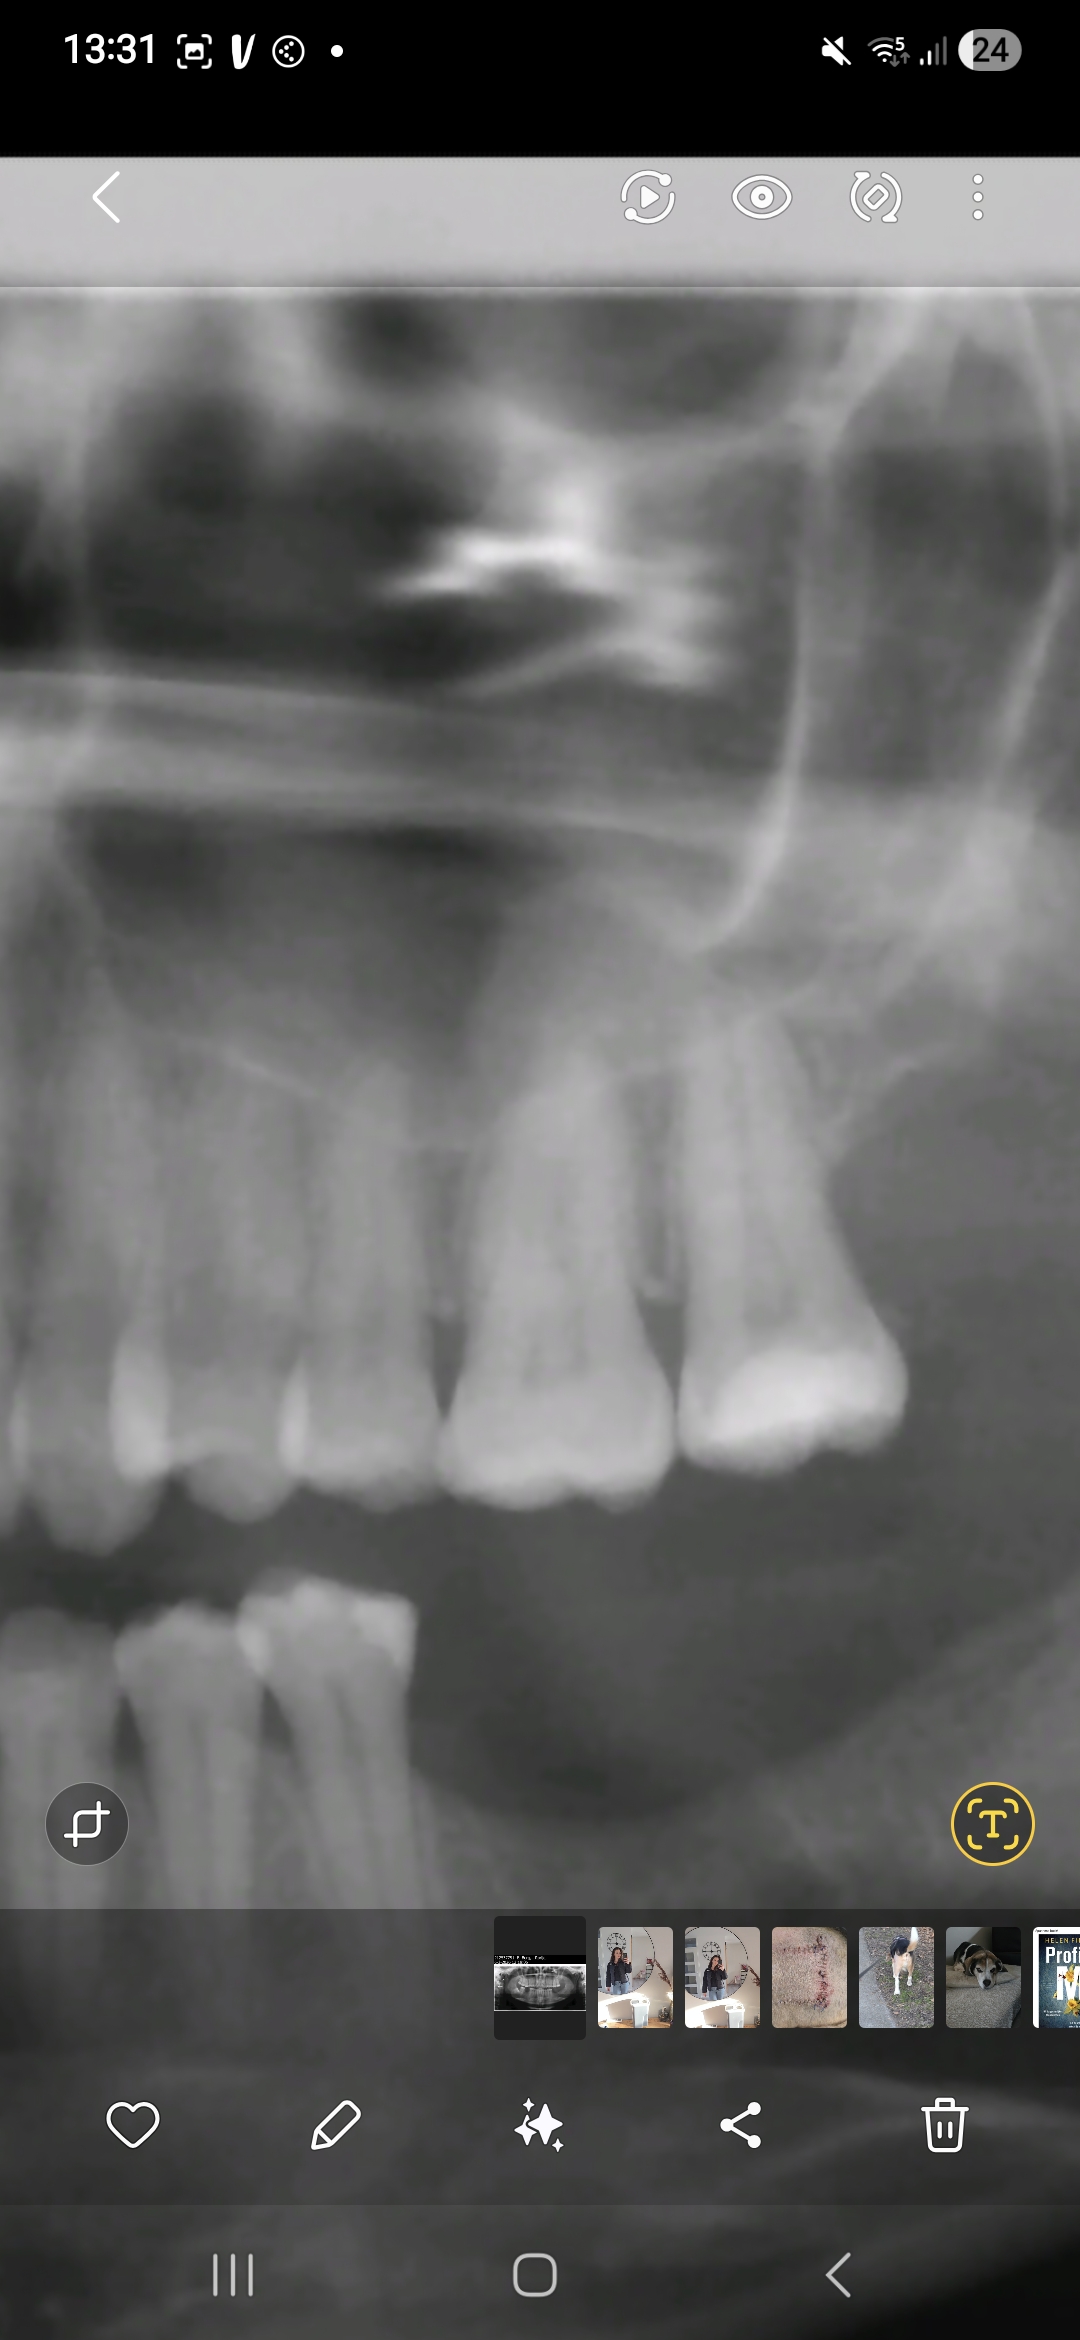

Ik heb al 3 weken kiespijn links bovenin.

Ben al 2 verschillende tandartsen geweest en geen 1 die kan iets vinden.

Hebben jullie een idee? Gaat om de laatste 2 kiezen boven in.

Wazige foto. Mogelijk , vanwege diepe vulling laatste kies, ontsteking wegens afsterven zenuw.

Testen door warm/koude prikkels en /of proefboren zonder verdoving om diagnose te bevestigen. Waarschijnlijk is de kies niet koude of warmte gevoelig of anders wel warmte gevoelig.

Indien "dode" zenuw dan of:

-kies verwijderen omdat ertegenover geen kies zit, dus geen functie..

-Wortelkanaal behandeling.